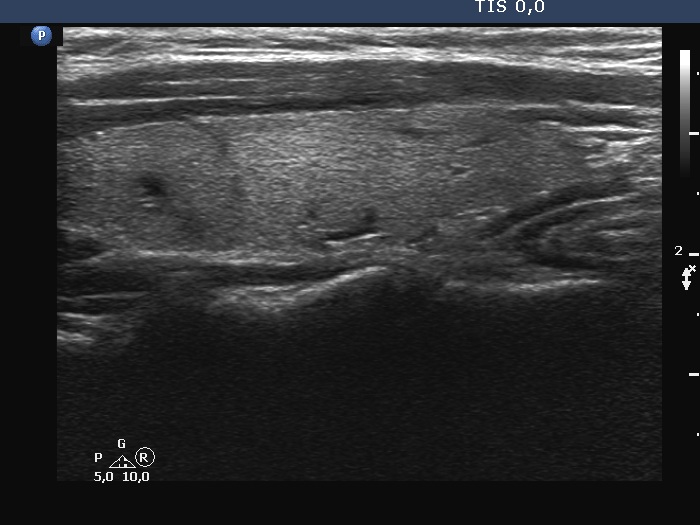

Thyroid cancers - case 727 (ultrasonographic picture 8)

Left lobe, longitudinal scan. None of the discrete lesions shares clinical or oncological importance.